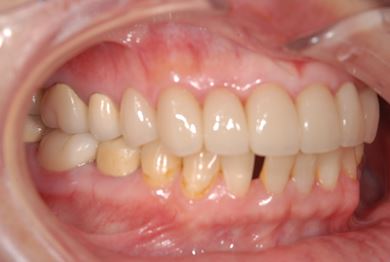

| 性別/年齢 | 女性 / 51歳 | ||||||||||||||||||||||||||||||||

| 治療方針 | セラミック治療にて、審美的回復を行う。 | ||||||||||||||||||||||||||||||||

| 治療内容 | オールセラミッククラウン7本(オールセラミック用土台1本)、ハイブリッドセラミッククラウン10本(ハイブリッドセラミック用土台9本)、ハイブリッドセラミックインレー1本 | ||||||||||||||||||||||||||||||||

| 総治療費 | 961,800円 | ||||||||||||||||||||||||||||||||

| 治療期間 | 10ヶ月 |